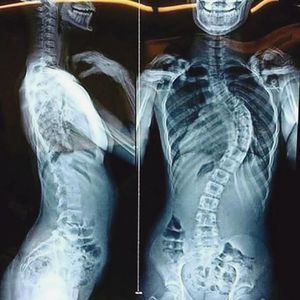

Here is a very interesting radiograph showing a case of scoliosis and dextrocardia.Scoliosis is an abnormal lateral curvature of the spine.Dextrocardia is a rare heart condition in which the heart points toward the right side of the chest instead of the left side.